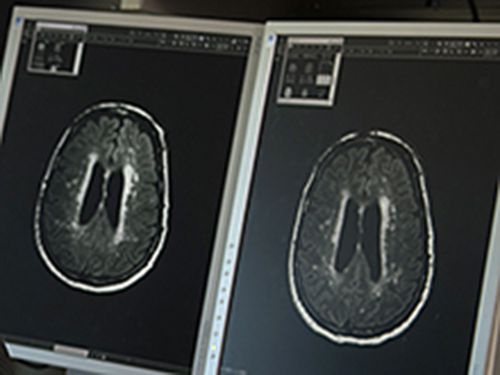

Оказывается, кости человека могут рассказать о состоянии его мозга. Это обнаружили исследователи из Медицинского университета Северо-Восточного Огайо. Исследование показало, что снижение минеральной плотности костной ткани перед появлением характерных симптомов болезни Альцгеймера связано с дегенеративным процессом в области ствола головного мозга.

Ствол мозга контролирует настроение, сон и обмен веществ. В этой части мозга вырабатывается серотонин, пишет Zee News. Снижение минеральной плотности костной ткани приводит к остеопорозу. Он повышает риск переломов, преждевременной смерти и снижает качество жизни людей с болезнью Альцгеймера.

Ученые пришли к выводу: оценив плотность костной ткани, можно определить риск деменции. Также специалисты подчеркивают, что необходимо исследовать роль серотонина в развитии болезни Альцгеймера.